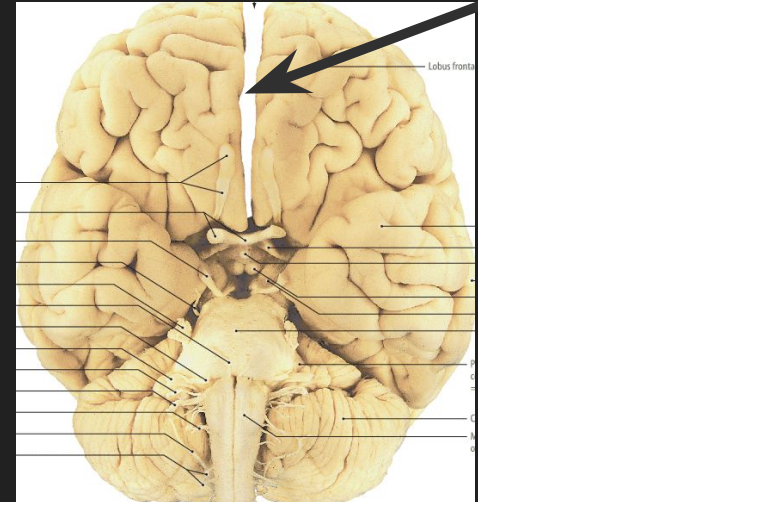

nucleus caudatus dex.

lobus parietalis Dex.

lobus temporalis sin.

a. carotis int. sin.

medulla oblongata

mesencephalon

hippocampus dex.

tonsilla cerebelli sin.

pyramis sin. medullae oblongatae

chiasma opticum

corpus mamillare dex.

a. basilaris

sulcus lateralis sin.

sulcus centralis sin.

pons

crus cerebri Dex.

corpus pineale

corpus callosum

radix n. trigemini sin.

ventriculus IV

Vermis cerebelli

hemisphaerium dex. cerebelli

Aquaeductus mesencephali

Crus cerebri sin.

Thalamus Dex.

hypophysis

plexus choroideus ventriculi III

nucleus lentiformis dex.

capsula interna sin.

ventriculus lateralis dex.

septum pellucidum

Insula Dex.

lobus frontalis dex.

lobus occipitalis sin.

fissura longitudinalis cerebri

tractus olfactorius dex.

bulbus olfactorius

medulla spinalis

ventriculus III